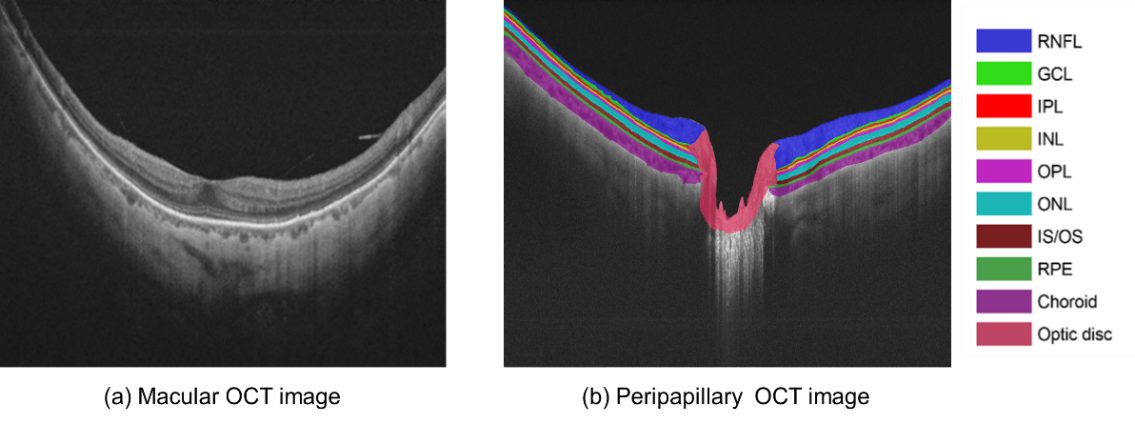

Figure 1: The comparison between (a) macular OCT image and (b) peripapillary OCT image. The peripapillary image is manually segmented. Ten labels including RNFL, GCL, IPL, INL, OPL, ONL, IS/OS, RPE, choroid, and optic disc are used and annotated by different colors. The layer structure follows an arrangement that the optic nerve head is located in the center of the image, while much thinner retinal layers are stratified on both sides.

In this manuscript, we report our recent study on explicit exploiting the prior knowledge existed in the peripapillary OCT images. We argue that all peripapillary OCT images obtained by following a strict clinical protocol should share a similar anatomical arrangement: the optic nerve head, which is a large structure, is located in the center region of the image, while much thinner retinal layers are stratified on both sides, as shown in Fig. 1. Inspired by Jamal et al.’s work that uses a graph to represent the domain knowledge and the structural relationship of the tissues [39], we designed a novel multi-scale graph convolutional network (GCN)-assisted two-stage network for joint segmentation of retinal layers and optic disc in peripapillary OCT images to fully take advantage of the anatomical priors. To show the efficacy of the proposed framework, experiments were conducted on a collected peripapillary OCT dataset, which consists of a total number of 122 OCT B-scans from 61 patients, and another public dataset [40]. The proposed model demonstrated superior performances on both datasets in comparison with the baselines and the state-of-the-arts. In the future, we plan to integrate the proposed segmentation framework into a diagnostic workflow for early-stage glaucoma detection. The dataset and the source codes are now publicly available online at https://github.com/Jiaxuan-Li/MGU-Net.

In current study, 10 labels including retinal nerve fiber layer (RNFL), ganglion cell layer (GCL), inner plexiform layer (IPL), inner nuclear layer (INL), outer plexiform layer (OPL), outer nuclear layer (ONL), inner/outer photoreceptor segment (IS/OS), retinal pigment epithelium (RPE), choroid, and optic disc are manually annotated on the OCT dataset to facilitate the training procedure as illustrated in Fig. 1(b).